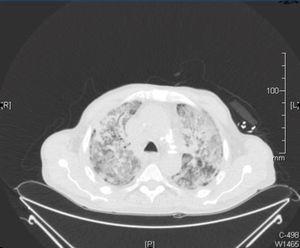

A computerised tomography (CT) scan was requested, along with a bronchoscopy and bronchoalveolar lavage and a PCR for cytomegalovirus (CMV) and sputum cultures, expanding the antimicrobial spectrum with sulfamethoxazole trimethoprim, liposomal amphotericin and ganciclovir. In the chest CT scan, we observed a localised mass in the right upper lobe with pleural contact and a marked decrease with respect to the previous CT scan, with a consolidative pattern and ground glass areas accompanied by a cobblestone pattern (Figure 2).

Figure 2. Chest computerised tomography scan.